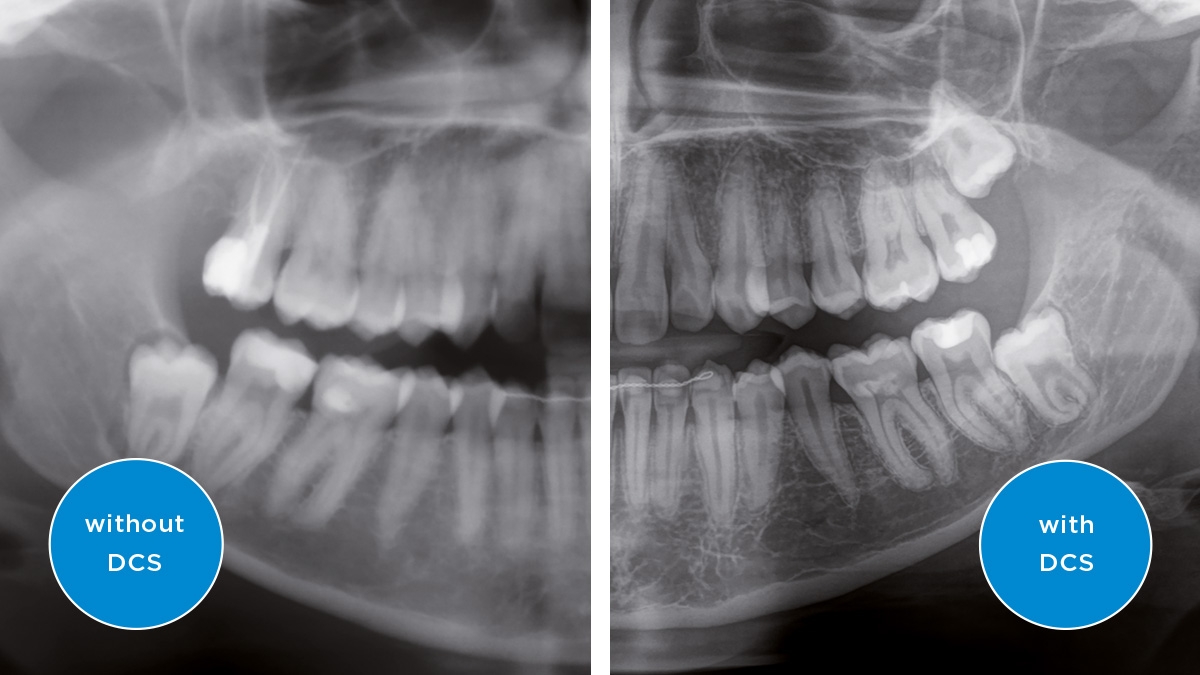

We developed a 10-point concept for easy patient positioning and X-ray imaging. Our concept is primarily about two things: high image quality and comfort for the patient and the assistant. This concept supports and provides the tools needed to ensure high-quality images for treatment analysis and focuses on ergonomics and comfort for the patient and assistant. The patented bite block technology, for example, automatically establishes the correct inclination of the patient's head, positioning the patient in the occlusal plane, partnering with the 3 point head fixation and firm handles to ensure stable positioning-limiting unnecessary correction scans.